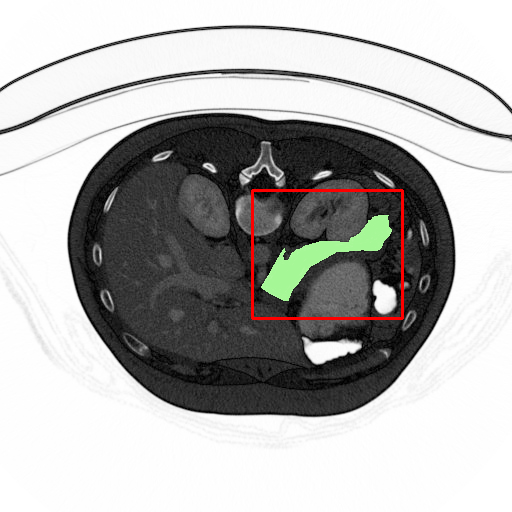

Refer to caption

Original

Ground truth

Prediction map

Overlayed region

Figure 11: 2D Illustration of segmentation result (best viewed in color). Two rows correspond to two different slices of pancreas. First column. Original input CT image, with pancreas area marked green, and bounding box given by localization process marked red. Second column. Ground truth pancreas map. Third column. Prediction map generated by our model. Last column. Overlayed prediction map and ground truth, with overlapped region marked yellow. The DSC reaches 94.32% for the slice on the first raw, and 88.67% for the second.

The final result is shown in Table I. After 50 epochs’ training, the mean DSC result of our model has reached 86.93±4.92plus-or-minus86.934.9286.93\pm 4.92, which outperforms the state-of-the-art 3D coarse to fine model [3]. With tight and accurate bounding boxes given by localization stage, mean DSC increases by 2.34%, and with the deformable structure, the worst case is able to perform better than ever. Note that the variance is relatively large. This is caused by the mixture of hard and easy cases. However for the evaluation of the same image, our method generally gets a higher DSC than method specified in [3][4]. The 2D illustration of segmentation result is shown in Fig 11.